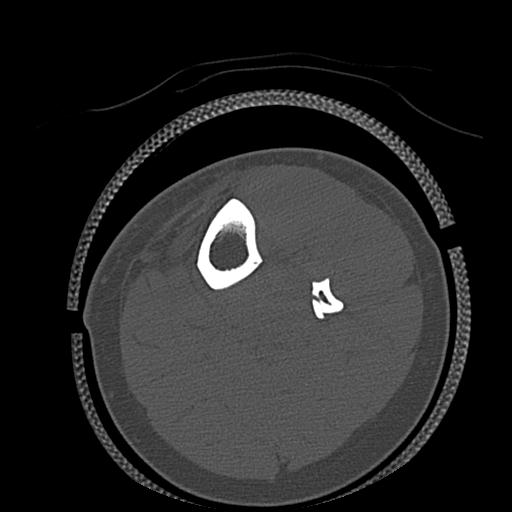

91983 11/16 左膝 2R 11/18 2R 55歳男性 脛骨骨切り術